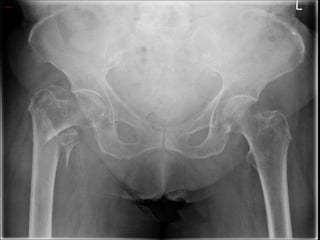

DIAGNOSTIC IMAGING

• X-ray is the standard diagnostic tool.

• When a hip fracture is suspected but not apparent on standard x-rays,

a technetium bone scan or a MRI scan should be obtained.

• MRI has been shown to be at least as accurate as bone scanning in

identification of occult fractures of the hip, and it will reveal a

fracture within 24 hours of injury.

DIAGNOSTIC IMAGING •X-ray is the standard diagnostic tool. • When a hip fracture is suspected but not apparent on standard x-rays, a technetium bone scan or a MRI scan should be obtained. • MRI has been shown to be at least as accurate as bone scanning in identification of occult fractures of the hip, and it will reveal a fracture within 24 hours of injury.

• #10 1. AP view of the pelvis . 2. AP and a cross-table lateral view of the involved proximal femur